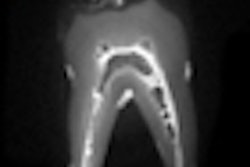

The Panoura 18S utilizes a CMOS sensor that can be transferred to an optional cephalometric arm, ImageWorks explained. With a user-adjustable focal trough, errant images can be brought back into focus after acquisition. At various speeds, the Panoura 18S can take a quick pan of six seconds, up to a 16-second pan for maximum resolution.

ImageWorks plans to introduce the 3D upgrade component for a multiple field-of-view imaging.